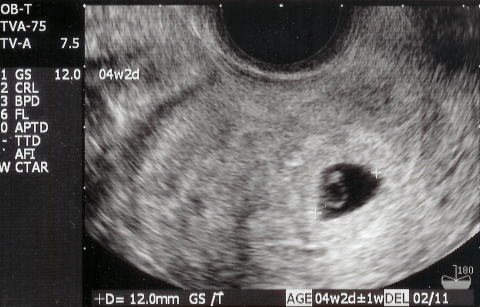

|  |  今日は健診です。依亜を幼稚園へ送った後、恭子お姉ちゃんとももちゃんも一緒に、電車で産院へ向かいました。30〜40分待ち診察。順調でしたが、ママは生理不順のため、排卵が遅れたということで、出産予定日が1/20から1/26に変更となりました。makotoの出産予定日は来年1月26日です。